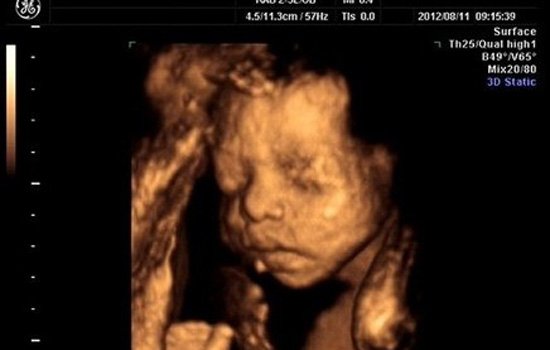

三维彩超

一般我们经常见到的普通b超和彩色b超,都是平面二维图像的。三维b超是立体动态显示的彩色多普勒超声诊断仪,它不仅具有二维彩超的全部功能,还可以进行胎儿头面部立体成像,可清晰地显示眼、鼻、口、下颌等状态,可协助医生直接对胎儿先天畸形进行诊断,包括表面畸形和内脏畸形,并能确定胎儿在子宫中的精确定位。

价格:三维彩超的功能更强大,所以价格也会更贵,不同的医院价格不一样,一般大概在230~300元左右,可能比普通彩超价格贵一倍,甚至更多。